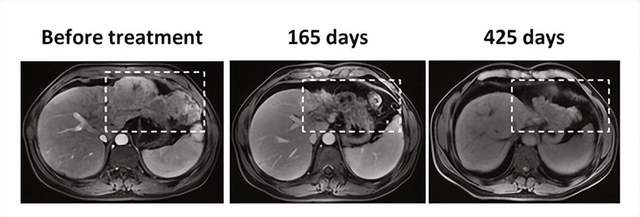

治疗165天后,其中1例患者出现肿瘤坏死,425例。 后天,肿瘤明显减少。